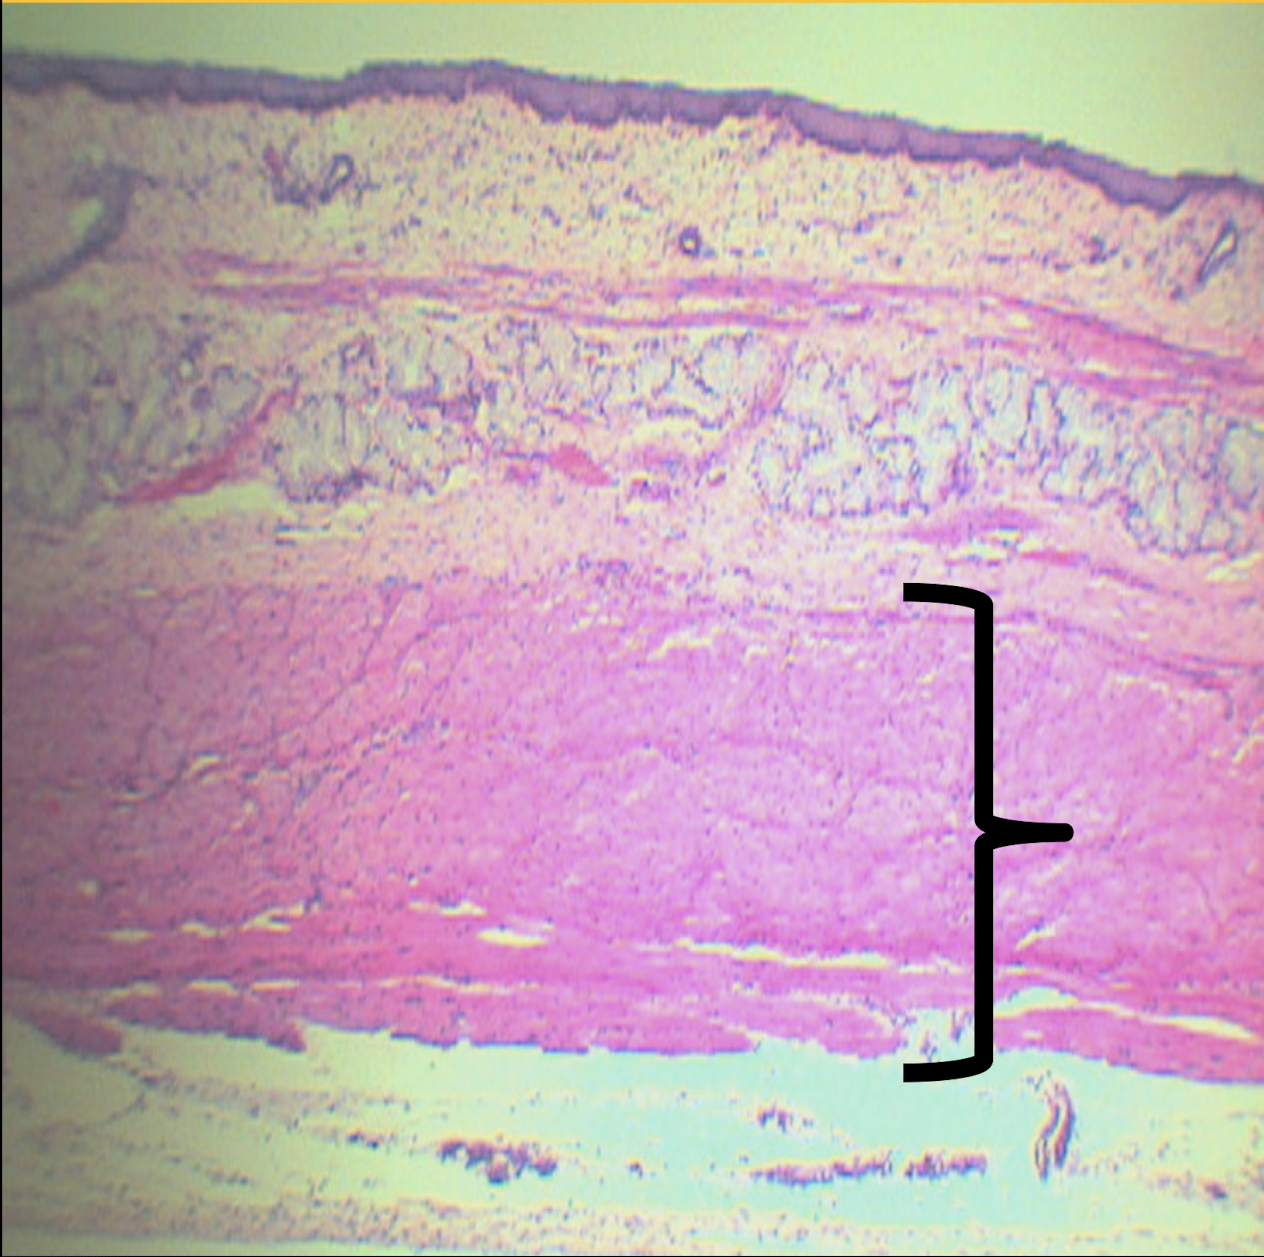

Scanner View of ESOPHAGUS

A: mucosa

B: submucosa

C: tunica muscularis

D: tunica adventitia/serosa

Identify the structure